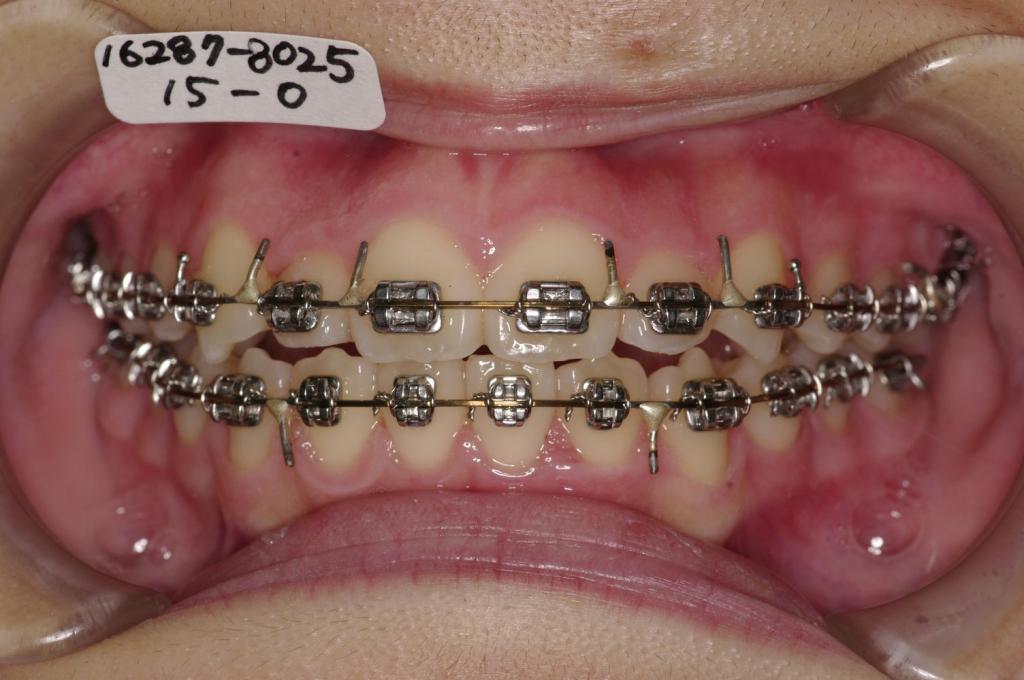

装置の種類及び治療法 診断:叢生

治療方法および装置:マルチブラケット装置

High pull J-hook headgear

抜歯:非抜歯

治療期間:12ヶ月

装置写真

治療前

歯並び・咬み合わせ・八重歯・乱杭歯の矯正治療前口内写真NO.1235

治療後

歯並び・咬み合わせ・八重歯・乱杭歯の矯正治療後口内写真NO.1235